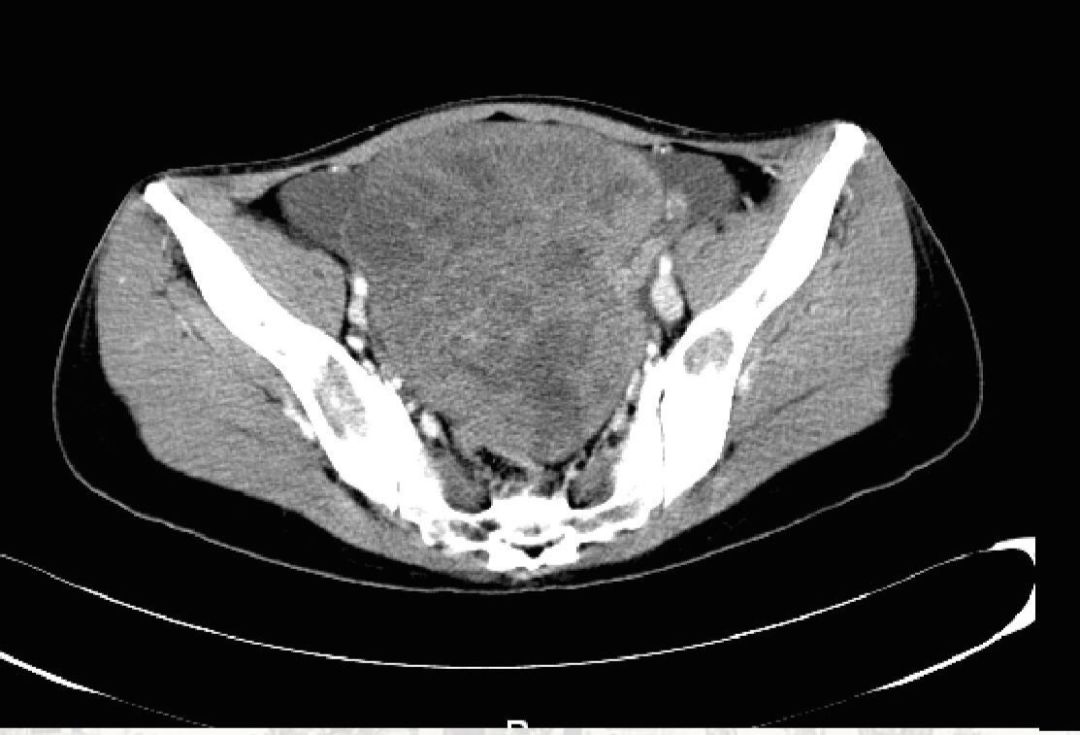

1、右侧盆腔巨大肿块,FDG代谢增高,右侧附件恶性病变考虑,请结合临床;2、所见全身骨多发骨质密度异常,部分可见骨质破坏,FDG代谢增高,考虑多发骨转移;3、胃小弯侧胃壁局部结节样增厚,FDG代谢轻度增高,结合病史,胃癌考虑;4、腹主动脉旁淋巴结,FDG代谢轻度增高,建议复查;腹盆腔积液;5、右侧扁桃体区钙化灶。6、纵隔多发淋巴结,FDG代谢略增高,炎性淋巴结考虑。7、左侧腹股沟软组织密度影,FDG代谢未见明显增高,腹股沟疝?。

图2  PET-CT影像